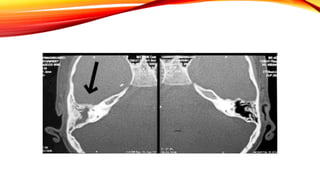

• Tomografia: Erosión/destrucción ósea

• Cultivo y tomografía de hueso temporal